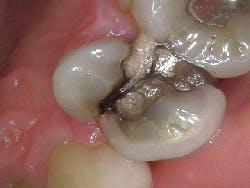

- Craze lines (figures 1 and 2)

- Fractured cusp (figure 3)

- Cracked tooth (figure 4)

- Split tooth (figures 5 and 6)